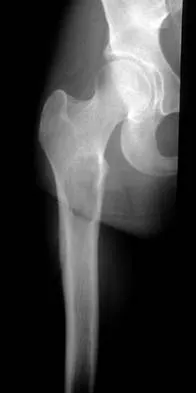

A 16-year-old boy has had thigh pain for the past several months. He denies any history of trauma. Examination reveals a large, deeply fixed, soft-tissue mass in the thigh. Laboratory results show an elevated erythrocyte sedimentation rate (ESR) and leukocytosis. A plain radiograph and MRI scan are shown in Figures 1a and 1b. Biopsy specimens are shown in Figures 1c and 1d. What is the most likely diagnosis?